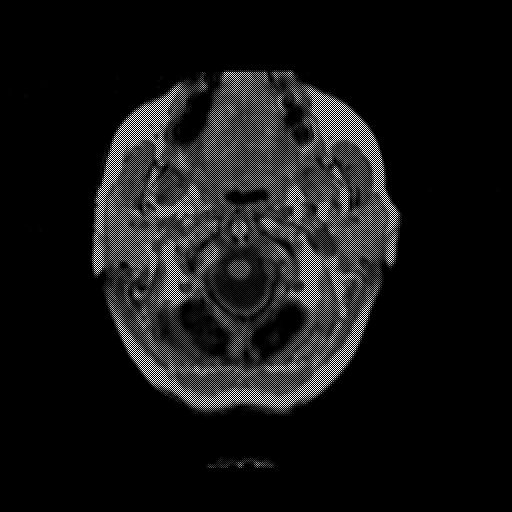

overlay: Slice 3

Slice 3

MRCBFCBF with

T1PDT2T1PDT2